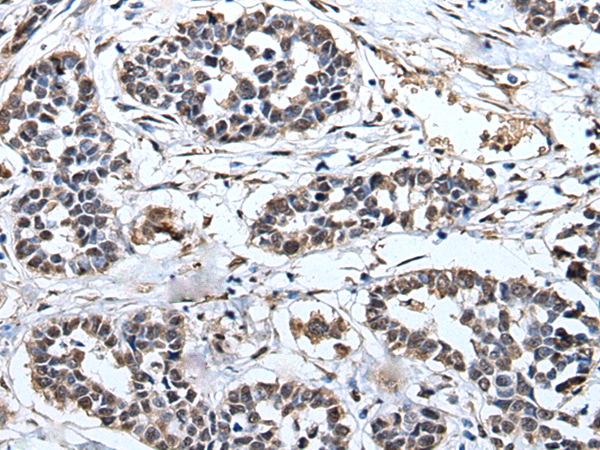

ELISA, IHC |

IHC positive control: |

Human liver cancer and Human esophagus cancer |

IHC Recommend dilution: |

30-150 |